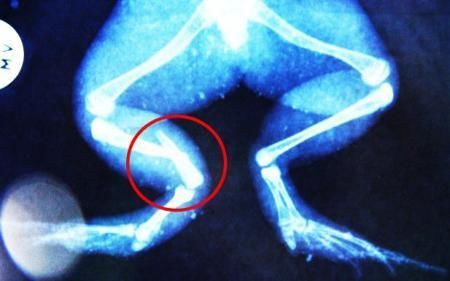

環(huán)球網(wǎng)4月2日報道 據(jù)《每日郵報》報道,上個月,南非大牛蛙布魯萊的右小腿被鄰居家的一只狗咬到,導致粉碎性骨折,現(xiàn)在經(jīng)過2個小時的手術(shù),它的斷腿已經(jīng)被接上,它也因此成為有史以來第一只通過外科手術(shù)用鋼針接上斷腿的青蛙。

布魯萊的主人,居住在南非約翰內(nèi)斯堡附近的62歲的安妮·米恩斯說:“我對這只青蛙如此關(guān)心,人們一定認為我瘋了,但是我無法眼睜睜看著它那么痛苦。青蛙因其靈活的腿腳而著稱,一想到布魯萊的腿里要留下一個薄金屬片,我就感到心痛。然而我知道,如果不進行手術(shù),布魯萊以后就沒辦法動彈了。因此我匆匆趕到獸醫(yī)那里,央求他給這只可憐的青蛙動手術(shù)。這位獸醫(yī)整天救助小貓小狗,他很難理解為什么我這么擔心一只青蛙,但是最終他還是答應(yīng)了給布魯萊做手術(shù)。手術(shù)后是幾個小時的焦急等待,我們希望它能快快蘇醒過來。不過現(xiàn)在它的傷口已經(jīng)愈合,又能在花園里跳來跳去了。X光照射顯示,它會恢復的跟以前一樣。”

野生生物專家安妮經(jīng)常為學校寫教材,她認為這是人類第一次通過手術(shù)給一只青蛙接斷腿。在手術(shù)開始階段,獸醫(yī)把少量給狗用的麻醉藥注入到這只青蛙體內(nèi),讓它失去知覺。然后他在布魯萊的斷腿上切開一個小口,把一根小鋼針植入腿里。最后獸醫(yī)給它縫了9針,把切口縫合在一起。僅僅幾周后,布魯萊就能在安妮家附近活動了。這只青蛙大約已有25歲,主要以嚙齒動物、蛇和其他青蛙為食。布魯萊所屬的牛蛙種群正在不斷減小,目前只能在非洲南部的濕地里才能看到這種青蛙。